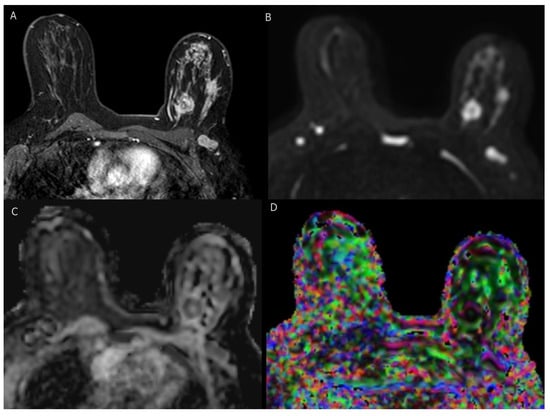

4.5. BI-RADS MRI Findings

4.6. Advancements in MRI Techniques

- Currently, MRI is the key technique for imaging breast cancer with the highest sensitivity (88–100%) among breast imaging modalities [49].